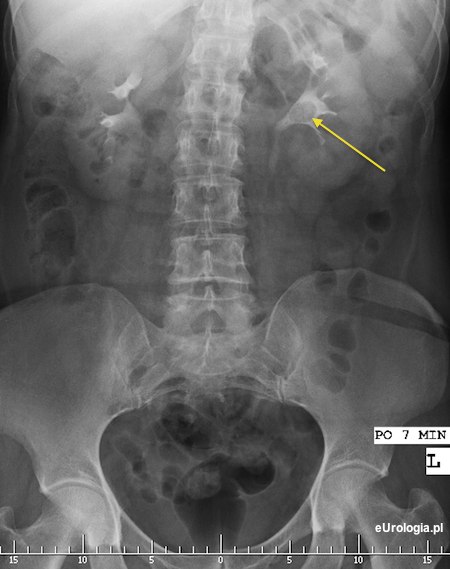

Fot. Złóg 12 mm w miedniczce nerki lewej - obraz urograficzny.